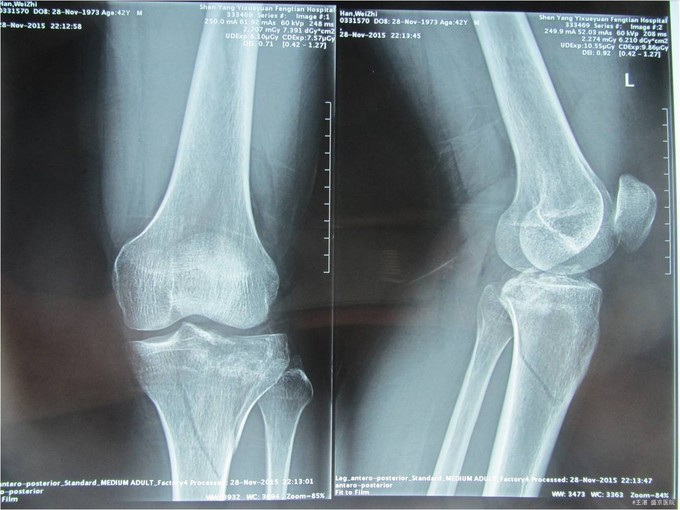

患者及家属自诉于2015年11月28日晚9点在沈阳市铁西区自己摔倒,摔倒后左下肢疼痛,活动受限,不能活动,急送至沈阳八院急诊,行DR提示:左胫骨近端粉碎性骨折。后送至我院急诊,行左膝关节CT后以“左胫骨近端粉碎性骨折”为主要诊断收入我科。患者轮椅入病房,无发热,无头晕头迷,无胸闷气短,无心慌心悸,无腹痛腹胀,受伤后排气正常,大小便未排。

专科查体:患者轮椅入病房。左小腿活动受限,压痛(+),叩击痛(+),双下肢皮肤感觉正常,足背动脉可扪及搏动,末梢血运良好,足趾活动灵活。 辅助检查:左膝关节CT:(我院,2015-11-29):左胫骨近端粉碎性骨折。